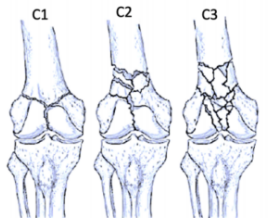

股骨遠(yuǎn)端骨折分型

股骨遠(yuǎn)端骨折可根據(jù)骨折模式、部位和膝關(guān)節(jié)受累情況進(jìn)行分型 ,AO/OTA分型常用于對(duì)這些骨折進(jìn)行分類。在每個(gè)類別中,骨折可根據(jù)復(fù)雜性和移位程度進(jìn)一步分類,對(duì)于與全膝關(guān)節(jié)置換術(shù)(TKA)相關(guān)的假體周圍股骨遠(yuǎn)端骨折,基于骨折移位和TKA股骨假體完整性的Lewis和Rorabeck分型(1997年)是最常用的分型:

A型:關(guān)節(jié)外骨折

不累及關(guān)節(jié)面

B型:部分關(guān)節(jié)內(nèi)骨折

累及部分關(guān)節(jié)面但保持一定的關(guān)節(jié)匹配性

C型:完全關(guān)節(jié)內(nèi)骨折

關(guān)節(jié)面完全破壞